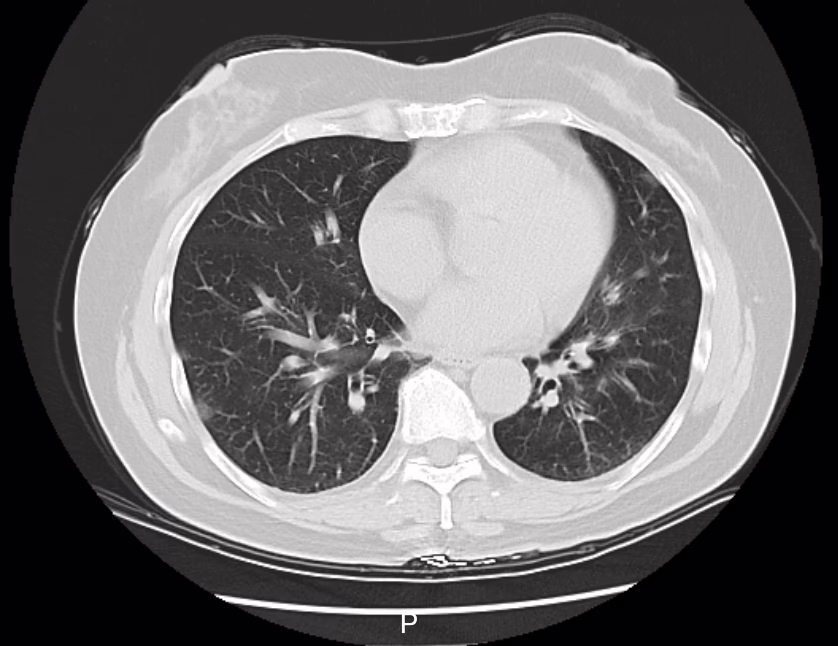

Ảnh minh họa